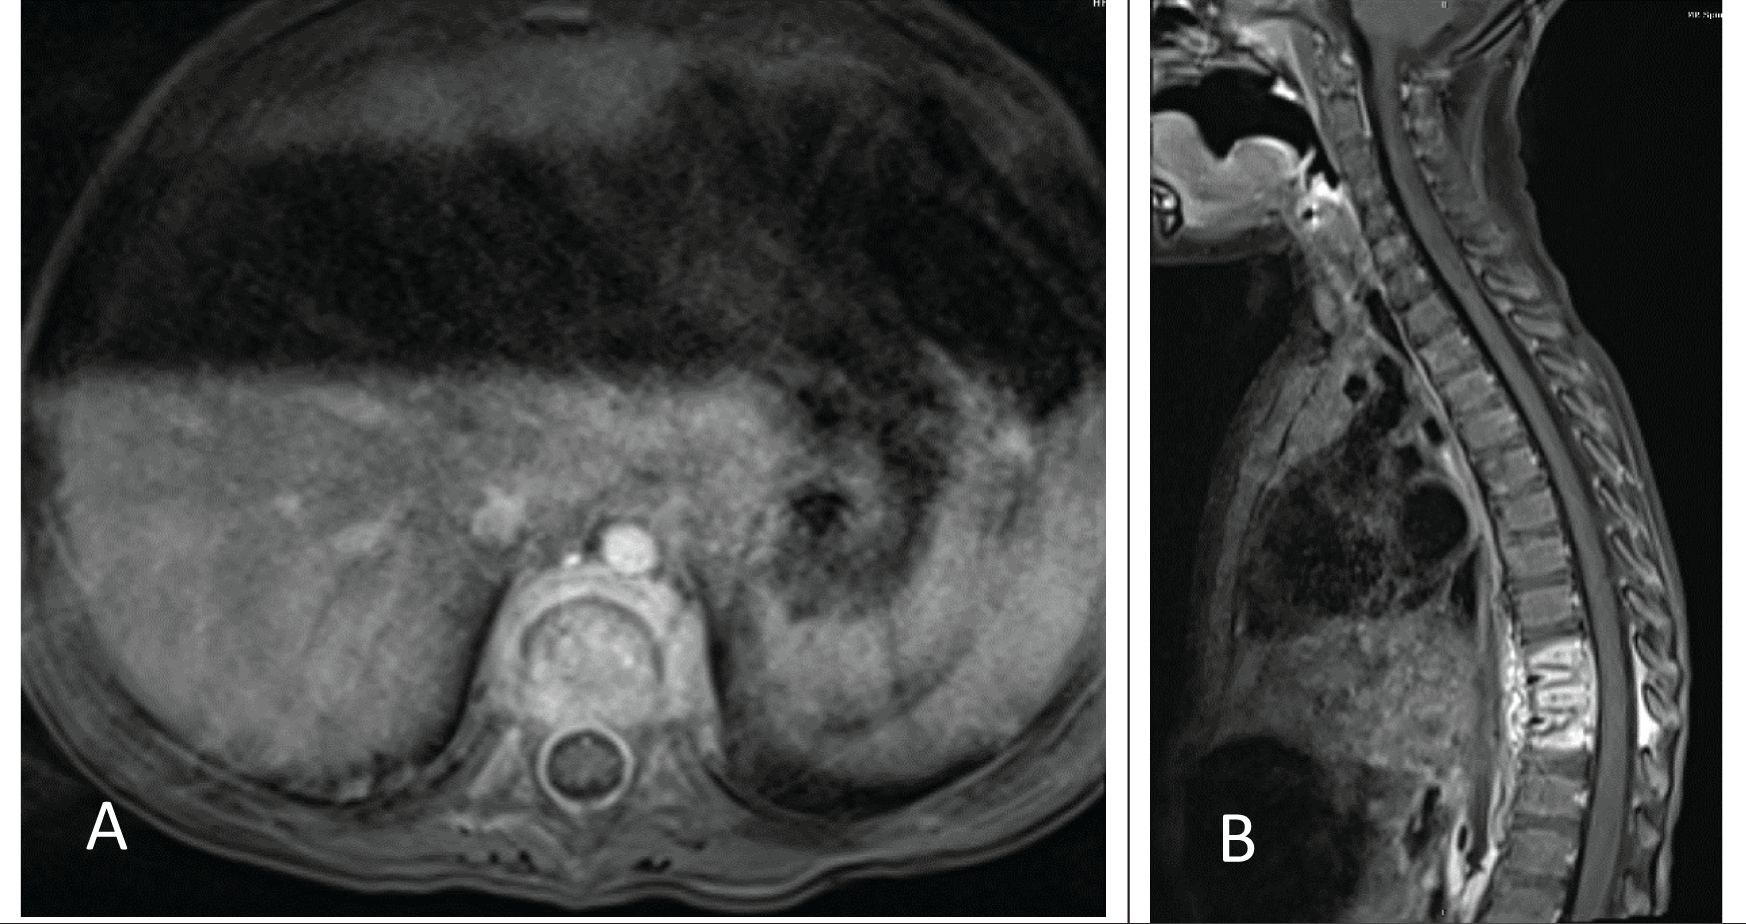

She then returned approximately 3 weeks later with malaise, an inability to stand upright, irritability, and pain on palpation of her back as well as a refusal to ambulate. On re-admission she was afebrile, and her laboratory investigation demonstrated an ESR 89 mm/hr (normal range: 0-20), and CRP <5 mg/L (normal range: 0-10). MR imaging of her spine demonstrated enhancement of T9-T11 with an epidural abscess (Figure 3A-B). A culture was obtained by computed tomography (CT)-guided needle aspiration and empiric therapy with meropenem (120 mg/kg/day intravenously divided every 8 hours for 2 days) was begun. Growth of P. aeruginosa was documented and a 6-week course of cefepime (150 mg/kg/day intravenously divided every 8 hours) was completed. Clinical improvement occurred; however, her laboratory investigation demonstrated an ESR 80 mm/hr (normal range: 0-20) and CRP <5 mg/L (normal range: 0-10) at the completion of therapy.

Axial (A) and sagittal (B) fat-saturated volumetric interpolated breath-hold examination (VIBE) postcontrast magnetic resonance imagery (MRI) images of the thoracic spine demonstrate multilevel thoracic osteomyelitis and discitis with associated epidural and paravertebral abscesses.